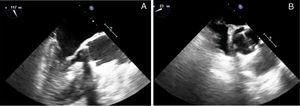

Infectious parameters began to decrease over the initial days of antibiotic treatment. Two-dimensional (2D) and three-dimensional (3D) TTE and transesophageal echocardiography (TEE) showed absence of endocarditis progression and an apparently unaffected, normal-functioning aortic prosthesis, with similar findings as in the initial echocardiography (Figure 1).

(A) 2-dimensional and (B) 3-dimensional transesophageal echocardiography. A 5-6 mm vegetation can be seen on the posterior surface of the aortic prosthesis, with a nodule persisting on the anterior surface of the mitral valve. No abscesses or other complications of infective endocarditis are observed and the mechanical aortic prosthesis discs are opening normally.